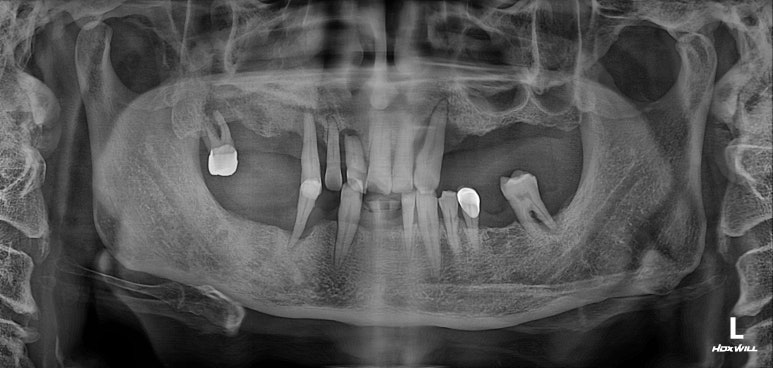

딱 봐도 치아가 많이 없으신 50대 남자 환자분입니다.

어떻게 그 동안 식사를 하셨는지 단번에 걱정이 되었던 분.. 개원 후 얼마 되지 않아 방문해셨던 분이라 더욱 기억에 남는 분입니다.

보통 만성치주염이 시작되면, 흔히 맨 뒤 어금니부터 상실하게 됩니다.

그 이유는 비교적 간단합니다. 맨 뒤 어금니가 가장 닦기 힘든 자리에 있기 때문이죠. 대부분 소홀해진 구강위생관리로 인해 생긴 치석 때문에 시작된 만성치주염으로 다수의 치아를 잃곤 하십니다.

사실 보고 있자니 마음이 심란합니다.

큰 어금니는 한개 밖에 남지 않았고, 그나마 작은 어금니도 여러개 소실되어 있네요.

아래 앞니도 없어졌고.....